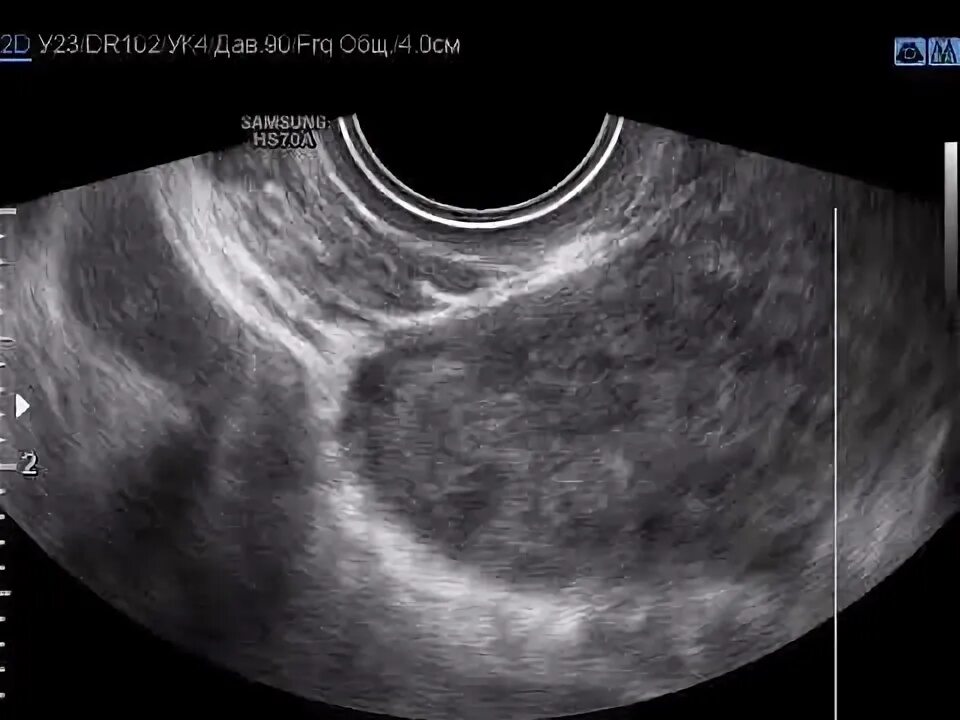

Что такое серозоцервикс в гинекологии у женщин